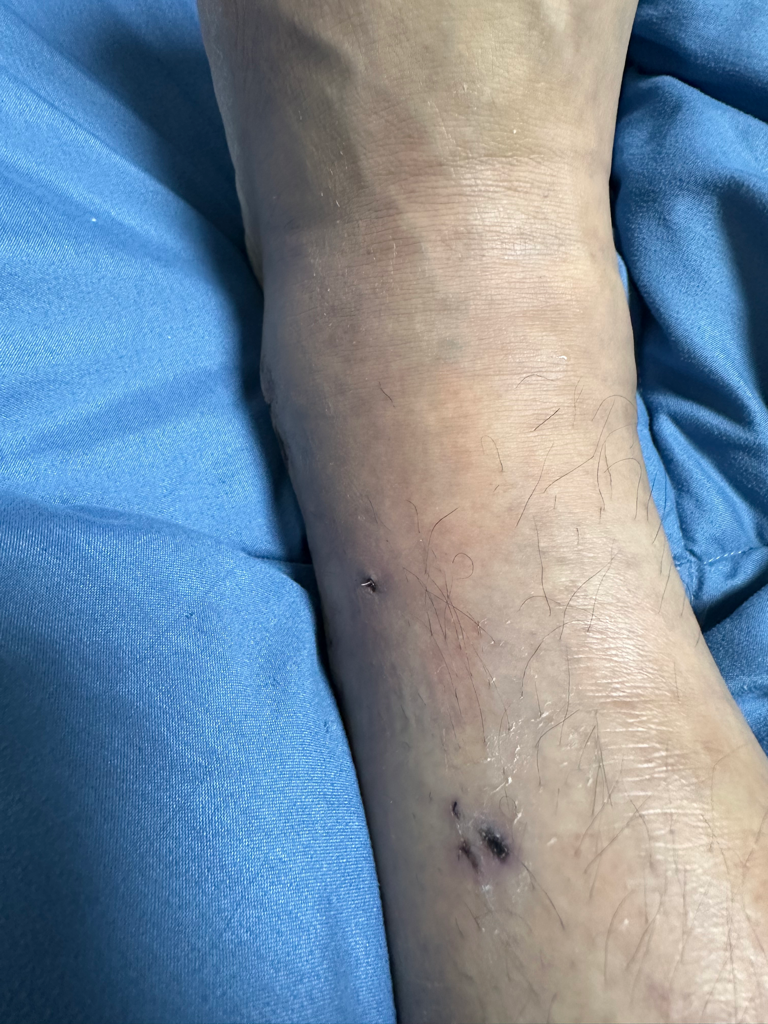

그리고 일주일간 입원 후 퇴원한 뒤 수술한지 2주가 지난 시점 지금까지 감고 있던 붕대를 풀고 집으로 돌아간 뒤 확인해보니

저렇게 낚시바늘같은것이 살을 뚫고 나와있었습니다

당장 주말과 크리스마스연휴라 내원을 하지 못하고 몇일이 지나 내원을 했더니 이런 쇳조각이 몸안에서부터 살을 뚫고 나왔던겁니다

자초지종을 물어보니 심을 박는 과정에서 판과 심의 마찰때문에 해당 쇳조각이 생성이 되었다고 하더라구요 백번 양보해서 쇳조각이 생성될 수도 있지만 이대로 봉합했다는 사실이 충격이었구요 설마 알면서 그랬다고는 상상하기싫고 몰랐다는것도 상상하기 힘듭니다